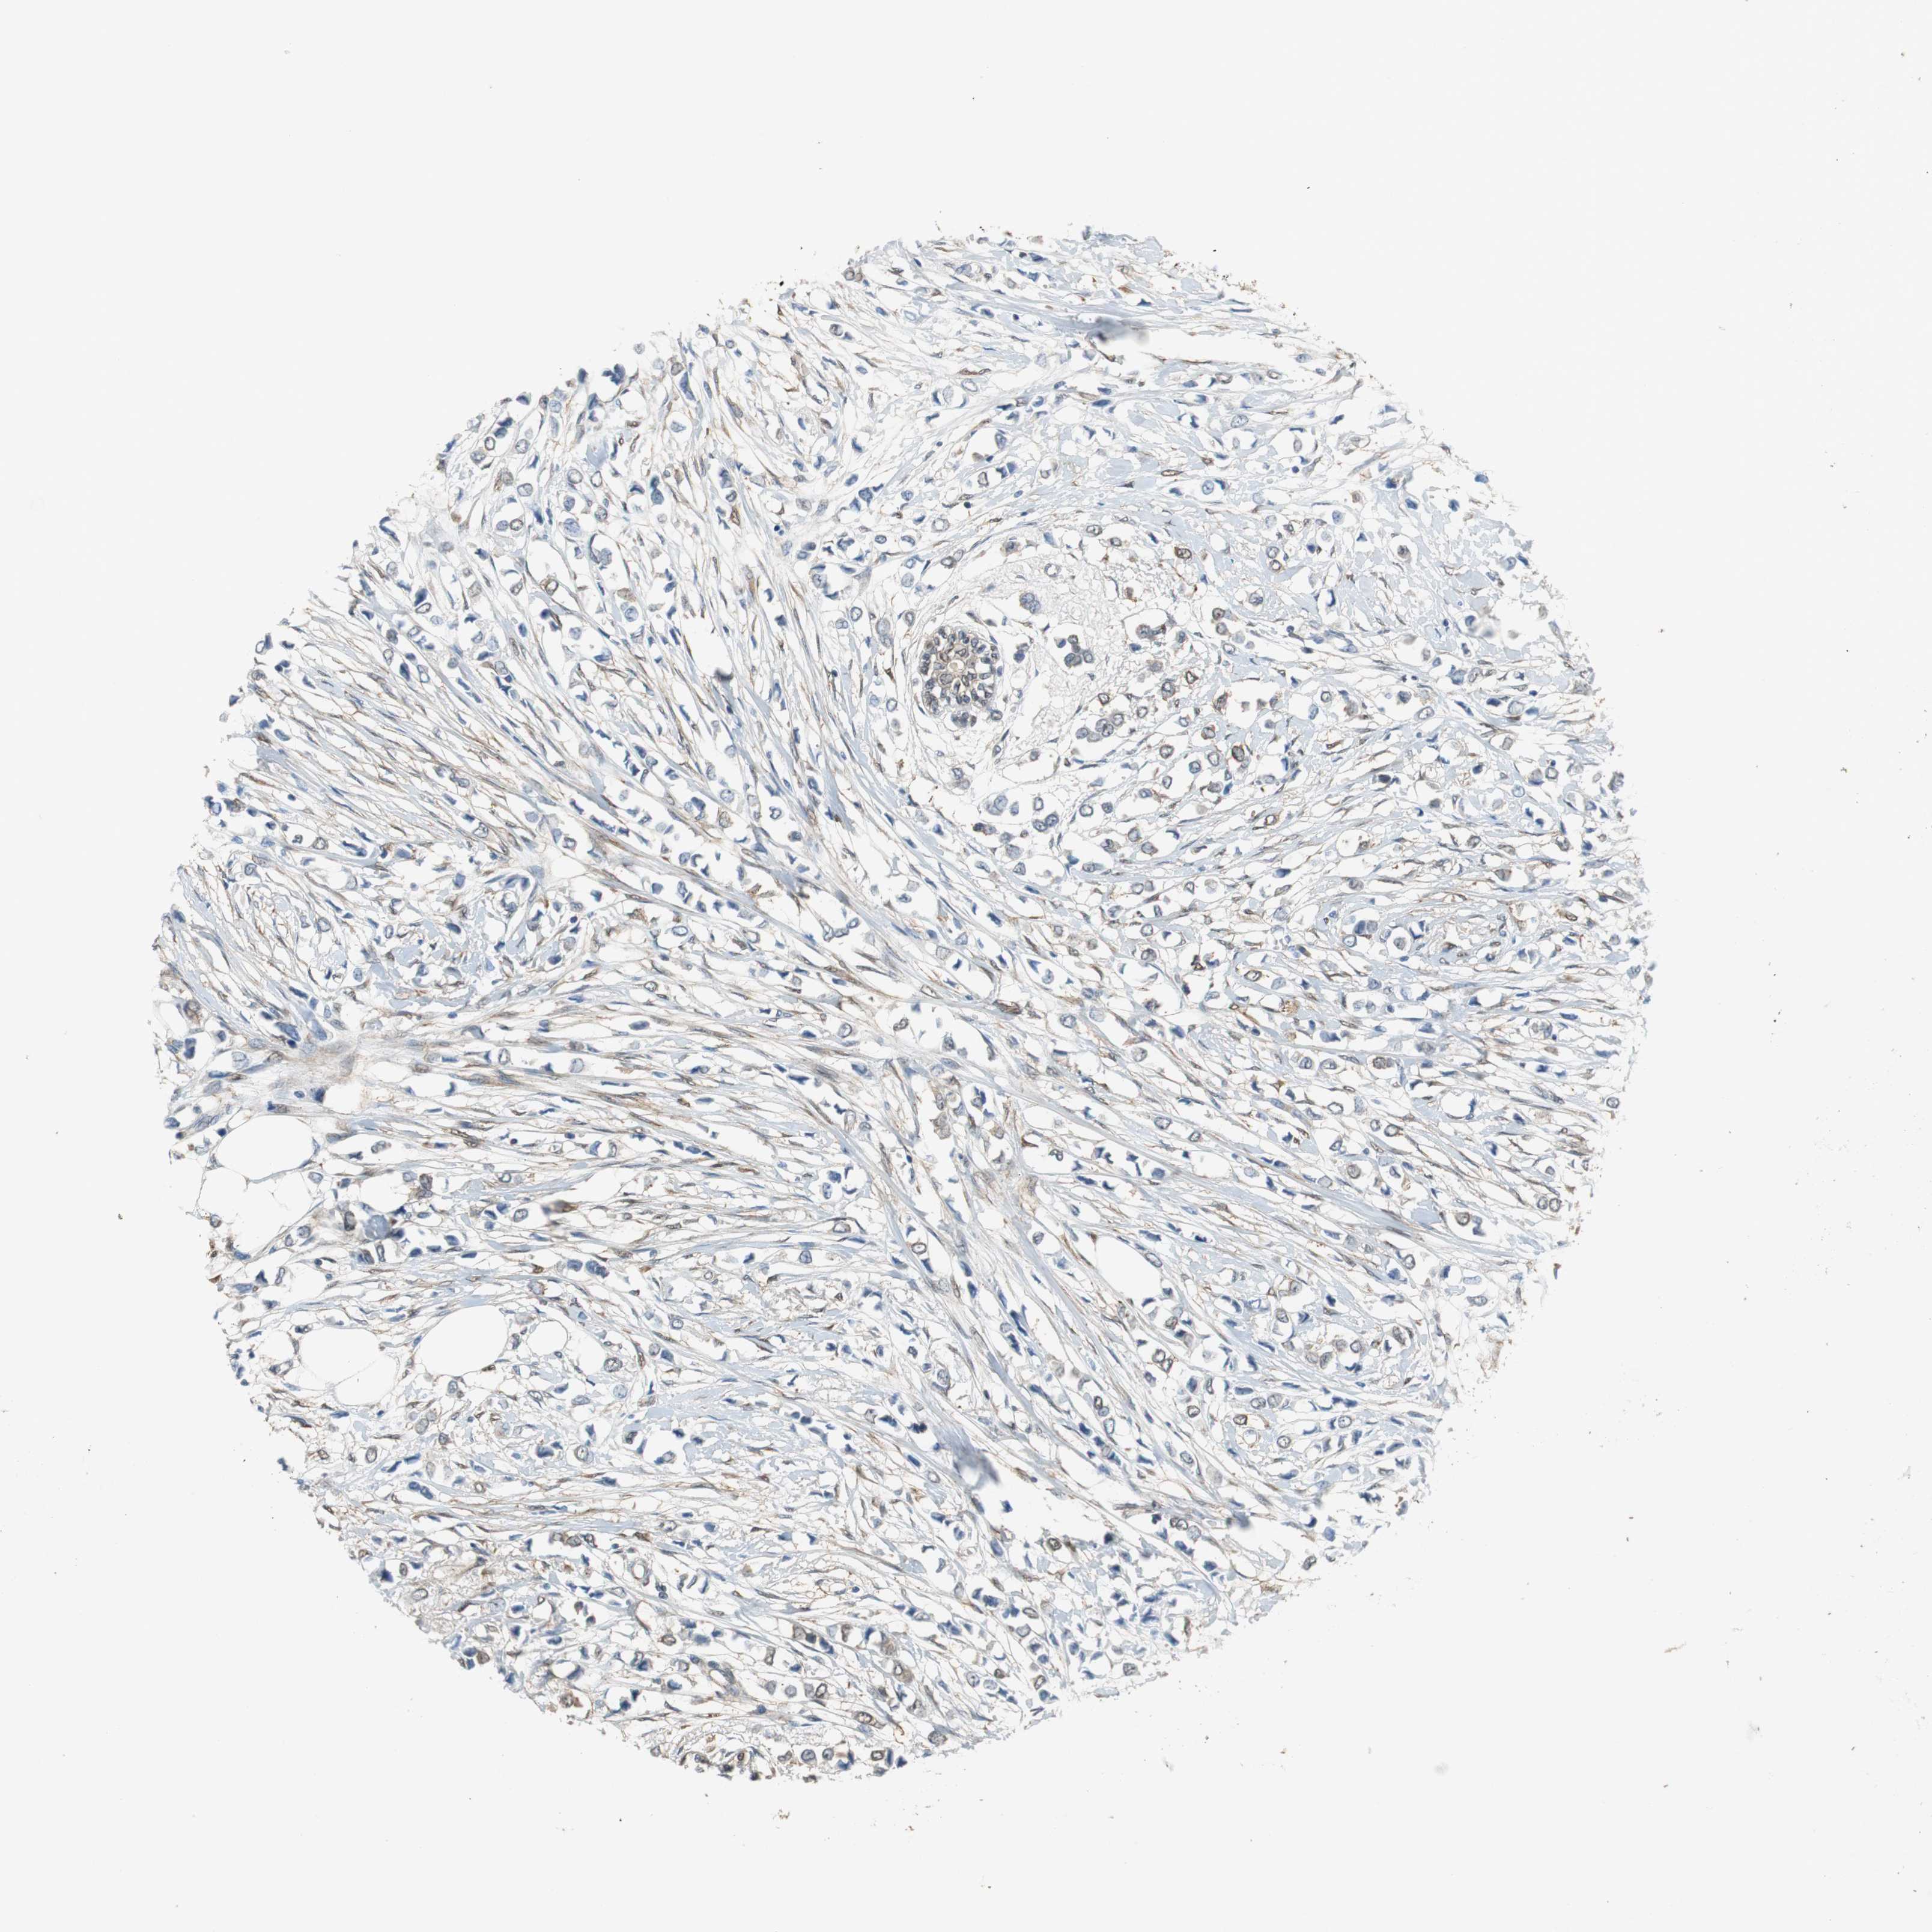

CANCER BREAST CANCER Show tissue menu

Breast cancer

Human cancer